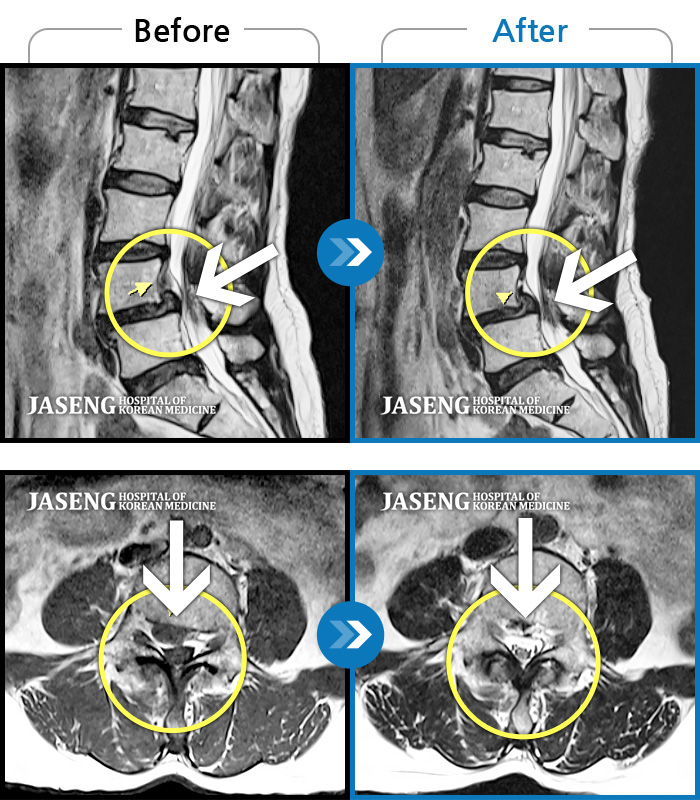

MRI 치료사례

허리 양측 골반에서 우측 허벅지 외측으로 통증, 5분 정도 기립 시 당기고 저리는 증상